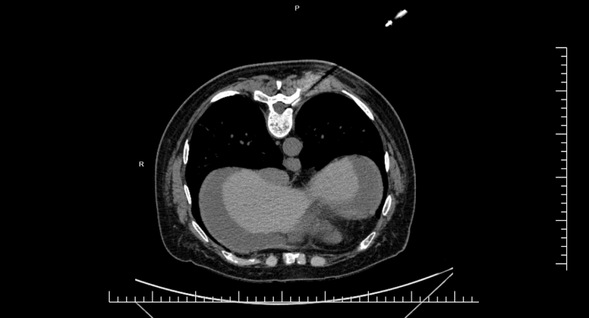

脉冲射频治疗是在CT定位下,准确找到受损神经,通过对神经进行调节,可以有效的治疗此类疼痛。

CT下定位穿刺针